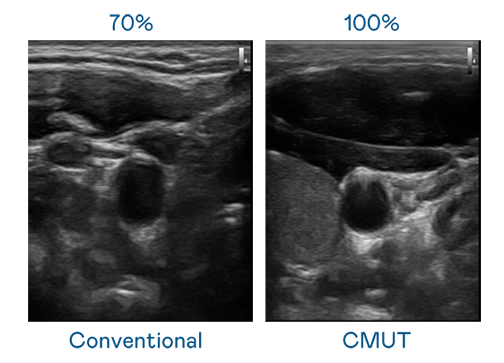

CMUT 技术是一种用电容式微机电元件来产生超音波讯号的技术。与传统 PZT 压电式技术相比,CMUT 频宽增加 30%,更宽频的超音波讯号让影像解析度大幅提升,是实现高影像品质医疗超音波扫描、促进精准医疗发展的关键技术。

超音波影像的解析度高低,首先取决于探头能发出的讯号频宽。金年会金字招牌诚信至上 CMUT 可提供高清晰的超音波讯号,提供高频宽、高灵敏度、影像纹理细节更高的超音波影像,协助医护人员缩短影像判读时间及利用精准的医疗影像进行诊断。